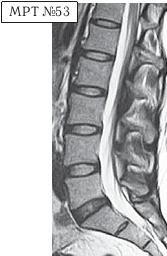

На МРТ № 53 — поясничный отдел позвоночника. На данном «контрольном» снимке, после устранения методом вертеброревитологии секвестрированной грыжи межпозвонкового диска в сегменте LV-SI, наблюдаются остаточные явления дегенеративного процесса. Но в целом состояние поясничного отдела позвоночника, отображённое на этом снимке, довольно хорошее, поэтому будем использовать его для сравнения как вариант нормы.